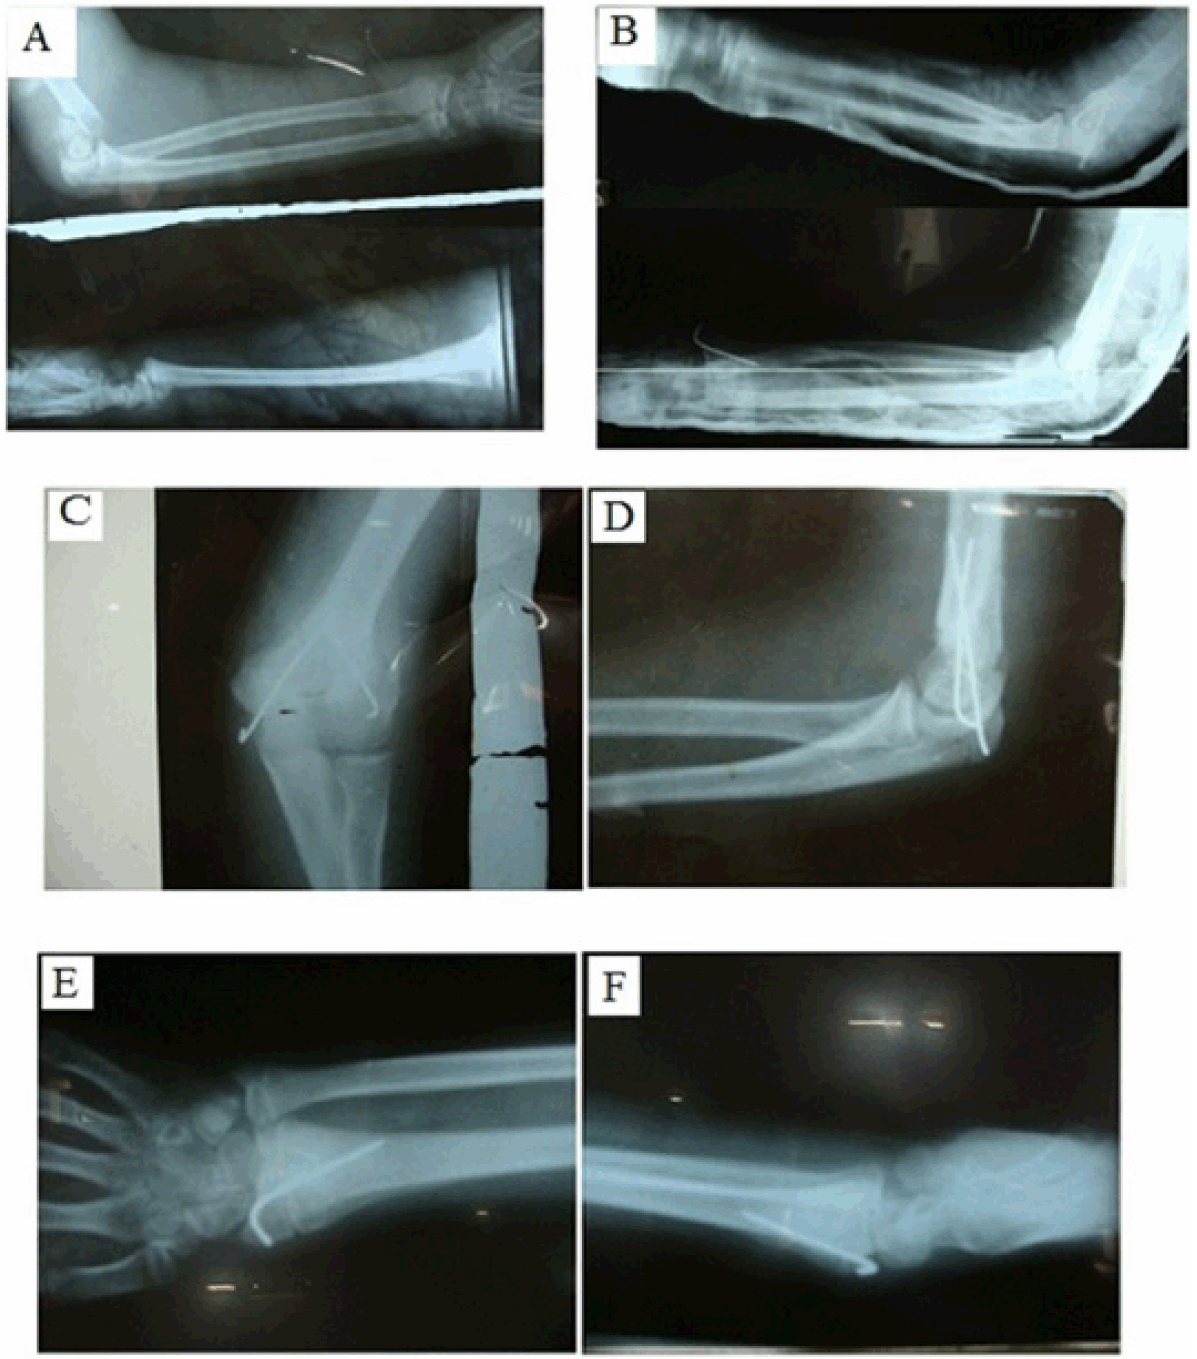

Figure 1: Radiographs showing ipsilateral supracondylar and distal and radius fracture. (A) Preoperative, and (B–F) Postoperative after pinning.